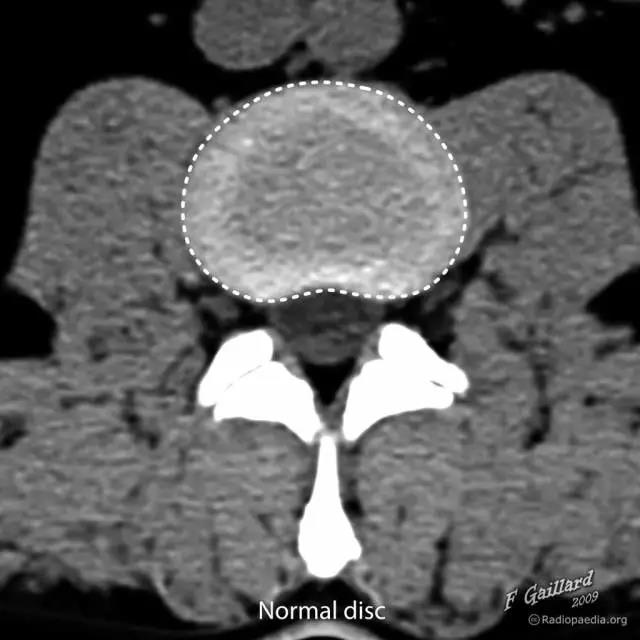

图 1 正常椎间盘示意图,椎间盘由周围的纤维环和中心的髓核组成

图 2 正常椎间盘在相邻两个椎体之间,周围不超出椎体的边缘